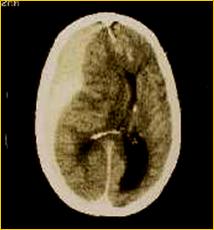

Le patologie che possono portare alla morte cerebrale sono l'emorragia cerebrale da rottura di un vaso intracranico, i traumi cranici ( incidenti stradali, ferite da proiettile ), le neoplasie cerebrali primitive.

EMATOMA SUBDURALE FERITA DA PROIETTILE

REPERTO ANATOMICO DI MASSIVA EMORRAGIA CEREBRALE